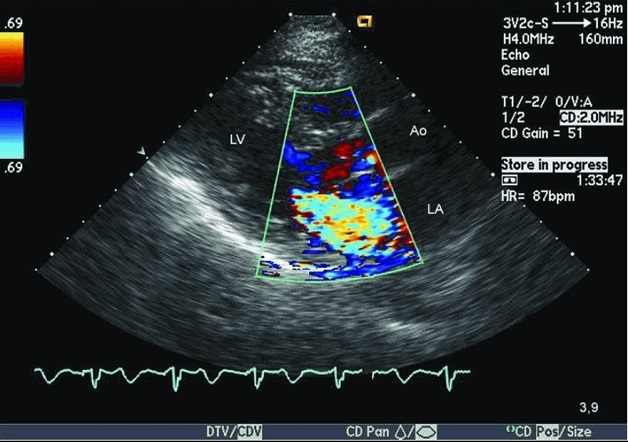

Siêu âm tim Doppler: Phương pháp này có thể đo vận tốc dòng máu ở các vị trí khác nhau trong buồng tim. Nhờ đó, có thể phát hiện dòng chảy bất thường trong các tổn thương van tim.

Ao (Aorta): Động mạch chủ

LA (Left Atrium): Nhĩ trái

LV (Left Ventricular): Thất trái